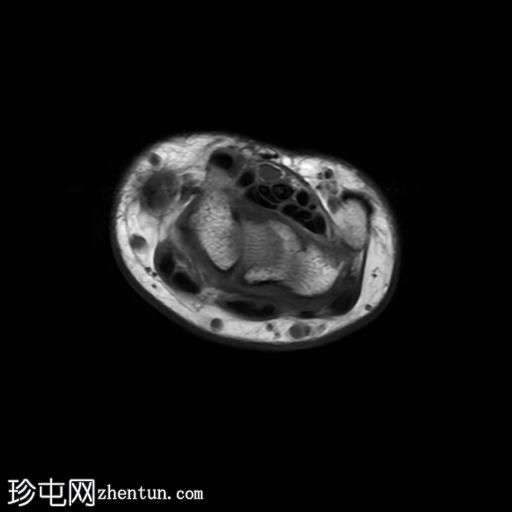

轴向PD值

脂肪饱和度

轴向

T1

MRI显示腕部第一背侧肌腱(拇长展肌和拇短伸肌)增厚,并伴有异常增厚的实质内液体信号。腱鞘内液体增多。

尺侧腕伸肌腱可见异常线性实质内液体信号增多,与板状间质撕裂相关。

MRI表现和临床表现提示De Quervain腱鞘炎。